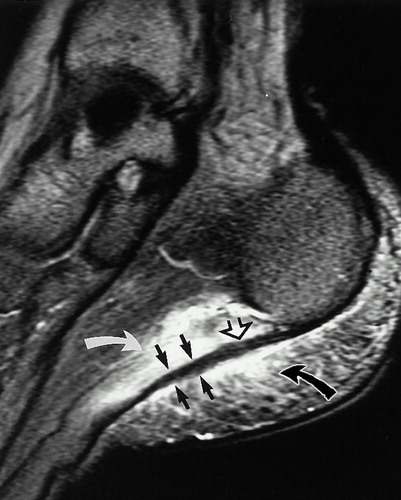

МРТ при плантарном фасциите. Хорошо видны воспаление и отек подошвенного апоневроза.